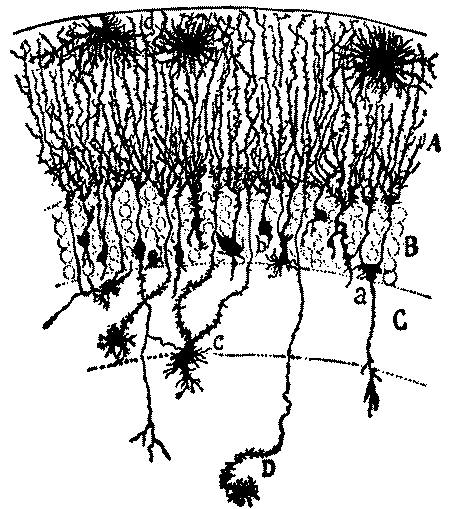

| 2. | Cortex of human brain illustrating complexity of the systems and plexuses of nerve fibers | 109 |

| 7. | Diagram of cells of cerebral cortex | 113 |

| 10. | Schematic frontal section through the occipital lobe illustrating manifold connections in a single lobe | 116 |

| 20. | Complexity of cell of the central nervous system | 131 |

| 21. | Section through the cortex of the gyrus occipitalis superior | 132 |